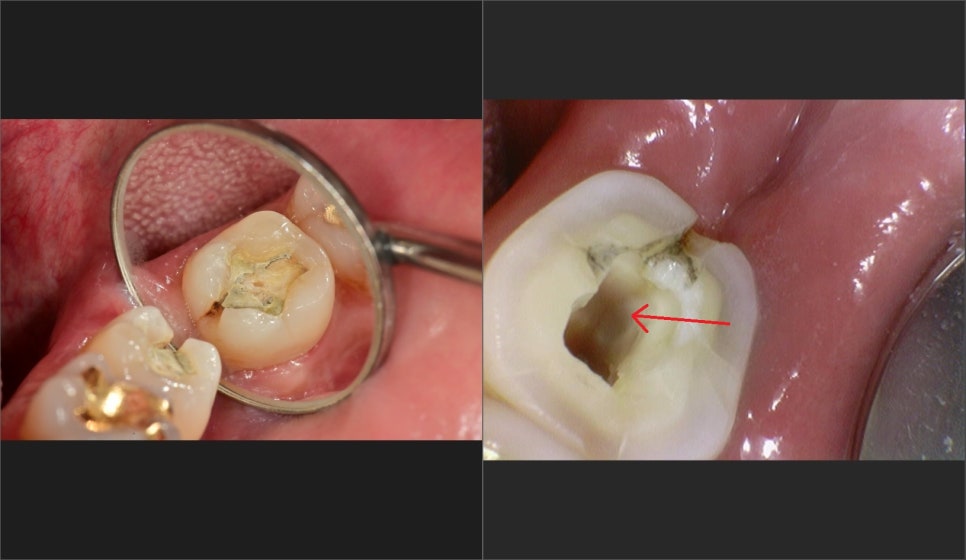

역시 뿌리 안쪽까지 크랙이 이어져 있습니다.

다시 비슷한 치아의 신경관 구조를 보면

단면이 이어져 있고,

실제 치아 내에서도 단독으로 입구가 존재하기도 하지만

계곡을 이루듯 신경관들이 연결이 되어있어서

최대한 많은 입구를 확보하는 게 가장 중요합니다.

다행히 신경관을 다 확보한후 신경치료가 끝난 사진입니다.